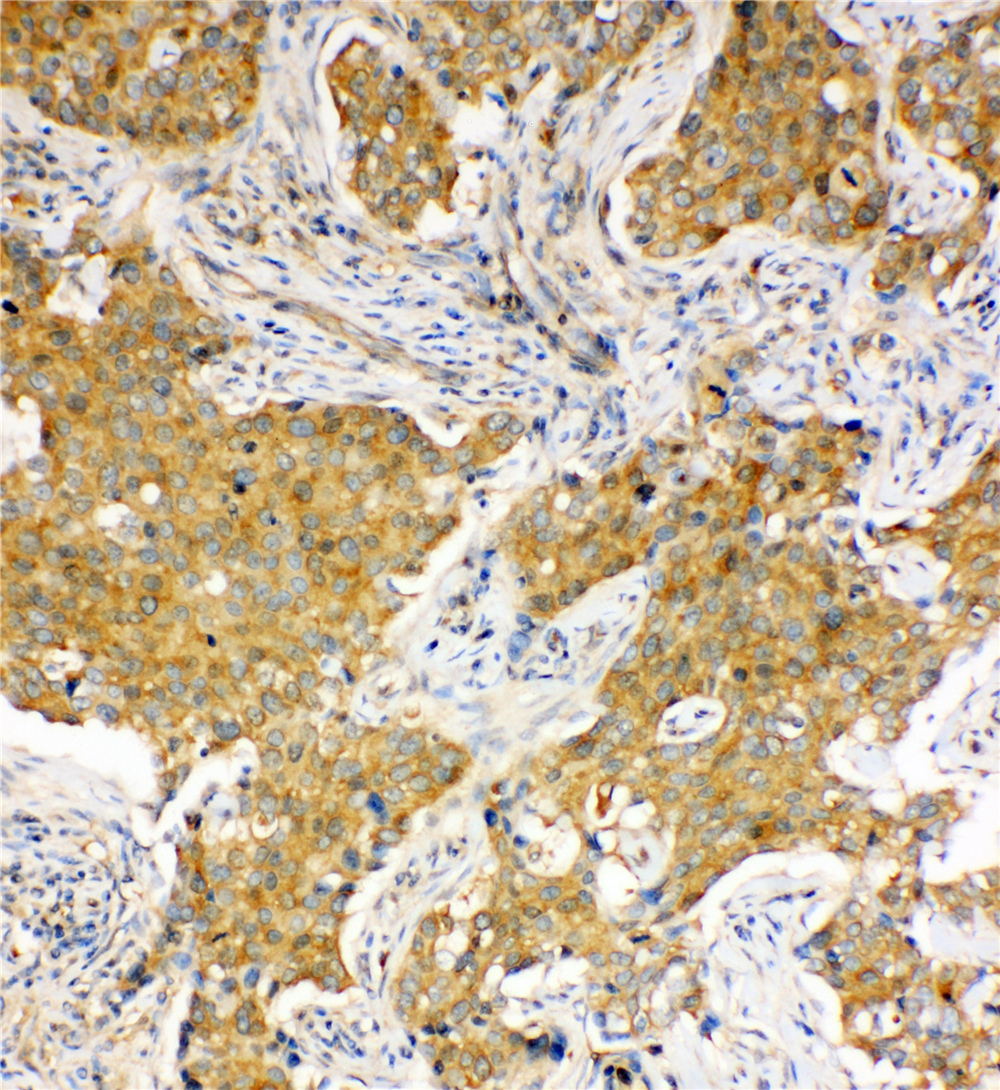

IHC analysis of HSC70/HSPA8 using anti-HSC70/HSPA8 antibody (BA2411).

HSC70/HSPA8 was detected in a paraffin-embedded section of human ovarian cancer tissue. The tissue section was incubated with rabbit anti-HSC70/HSPA8 Antibody (BA2411) at a dilution of 1:200 and developed using HRP Conjugated Rabbit IgG Super Vision Assay Kit (Catalog # SV0002) with DAB (Catalog # AR1027) as the chromogen.